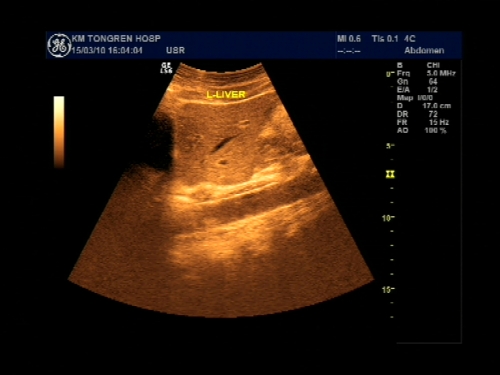

超声声像图能显示肝脏切面形态、大小、肝内实质结构、管道系统及肝周邻,并能根据肝内管道系统区分肝脏各叶、各段,对病变进行定位诊断。彩色多普勒超声能显示肝脏的血流,并能对肝脏的血流动力学参数进行测定,不仅能诊断肝脏的血管病变,还能了解正常肝脏及病变肝脏的血供及回流状态,目前已成为临床诊断肝脏疾病的常规检查方法。

纵断扫查

横断扫查

肝脏超声以肝内管道的一级、二级、三级分支未基础,将肝脏分为五叶8段:尾叶(Ⅰ)、左外叶上段(Ⅱ)、左外叶下段(Ⅲ)、左内叶(Ⅳ)、右前叶下段(Ⅴ)、右后叶下段(Ⅵ)、右后叶上段(Ⅶ)、右前叶上段(Ⅷ)